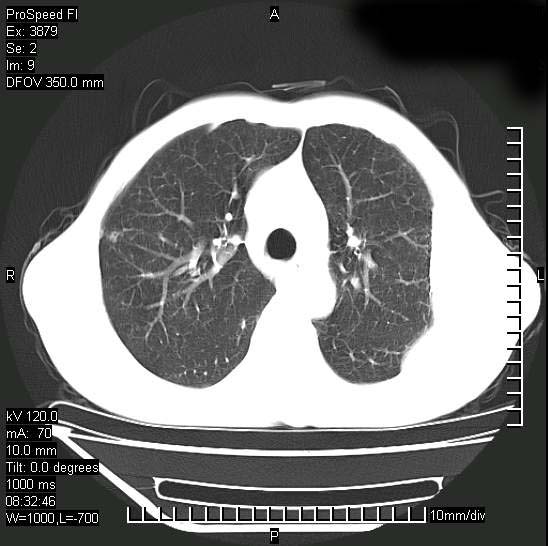

以下是引用312nanyang在2008-6-6 15:12:00的发言:[br]基本支持楼主意见[br]疑问?左下肺支气管旁的软组织(16层)密度怎么解释?淋巴结还是斜裂胸膜增厚所致?能否增强进一步检查